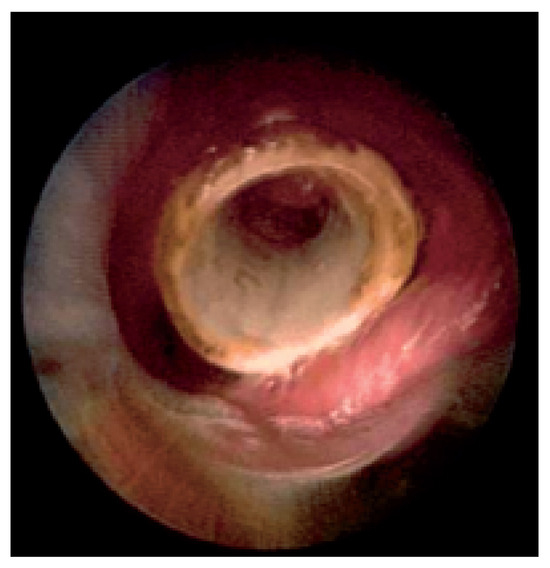

Endobronchiales Stenting

Patients with lung cancer often have bulky endobronchial disease, endobronchial extension, or airway compression. Many endobronchial treatment modalities are available to supplement traditional therapies for advanced lung cancer. Since the early 1980s, technical advances in interventional techniques have enhanced symptom-free survival and quality [...] Read more.

Patients with lung cancer often have bulky endobronchial disease, endobronchial extension, or airway compression. Many endobronchial treatment modalities are available to supplement traditional therapies for advanced lung cancer. Since the early 1980s, technical advances in interventional techniques have enhanced symptom-free survival and quality of life for patients with lung cancer. Although interventional procedures are not definitive therapies, they often relieve the strangling sensation produced by airway occlusion. For patients with respiratory symptoms associated with their disease, the stent placement provides symptom palliation and improves quality of life. The author reviews the use of several available endobronchial stents. Full article